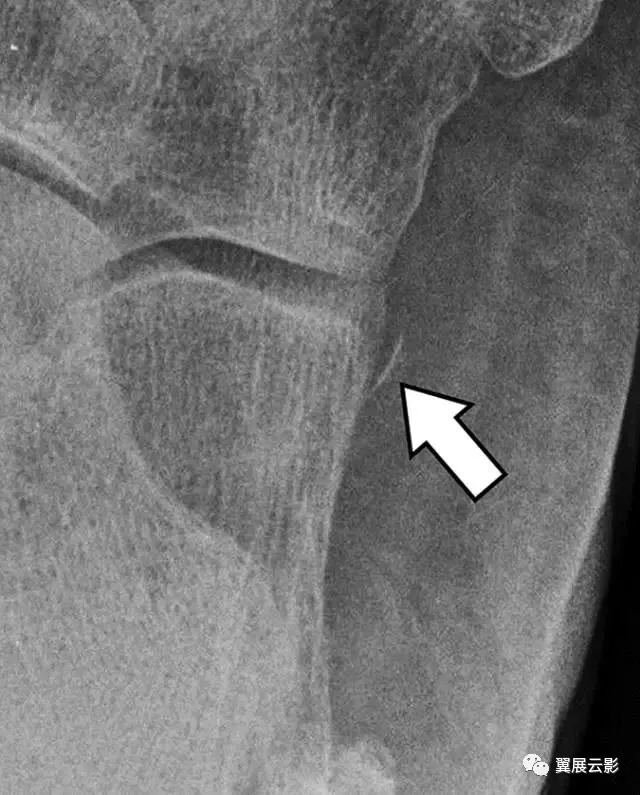

图7A-25岁的男子在滑雪时跌倒。侧位片显示跟骨骨折应于2型骨折(箭头)。